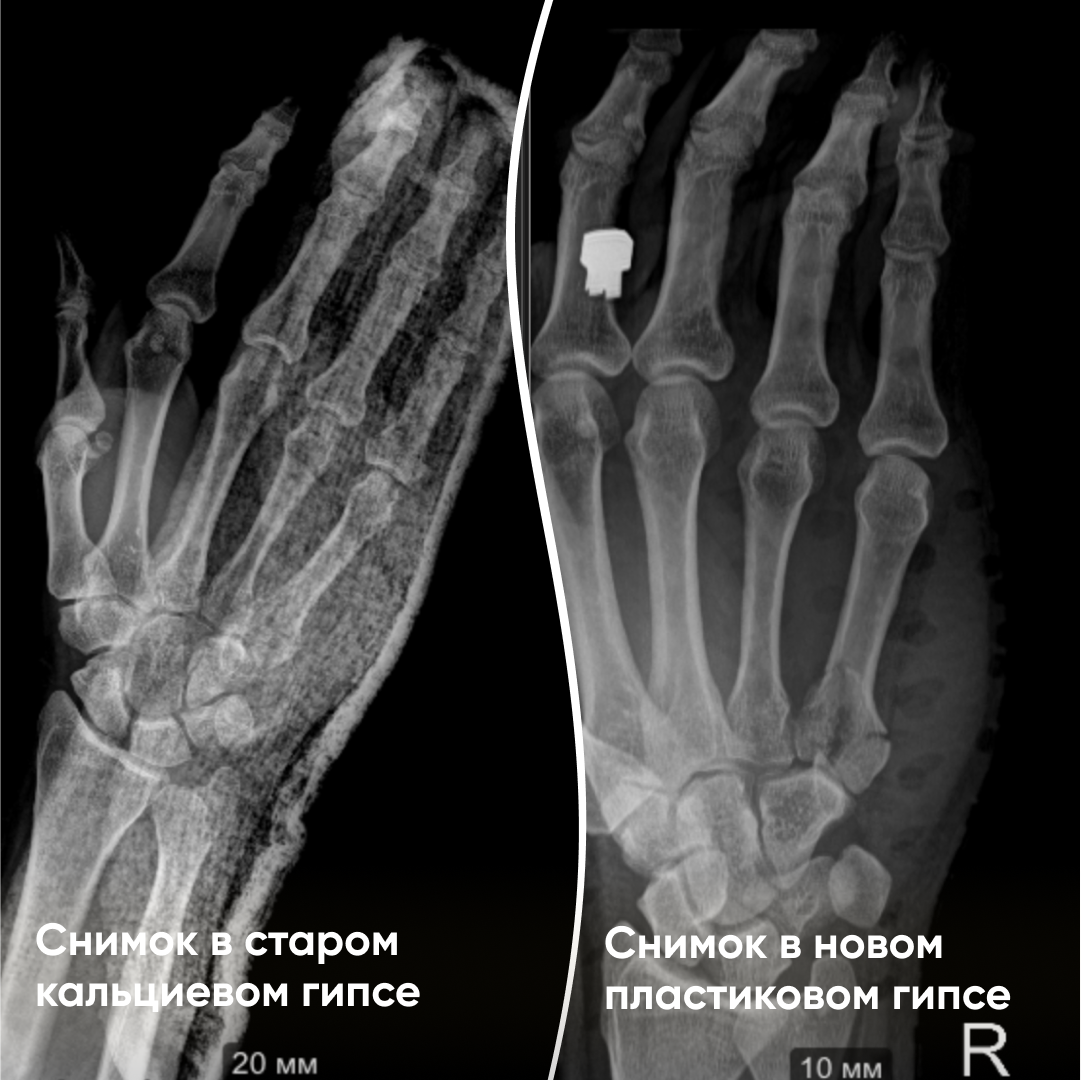

На фото — пример наложения пластикового гипса на правую кисть. Изготавливается на приеме за 15-20 минут травматологом-ортопедом. Вместо традиционного бинта здесь используется полиэфирный сетчатый материал.

На рентген-снимках можно увидеть, что пластиковый гипс не мешает проведению диагностики — он абсолютно незаметен.